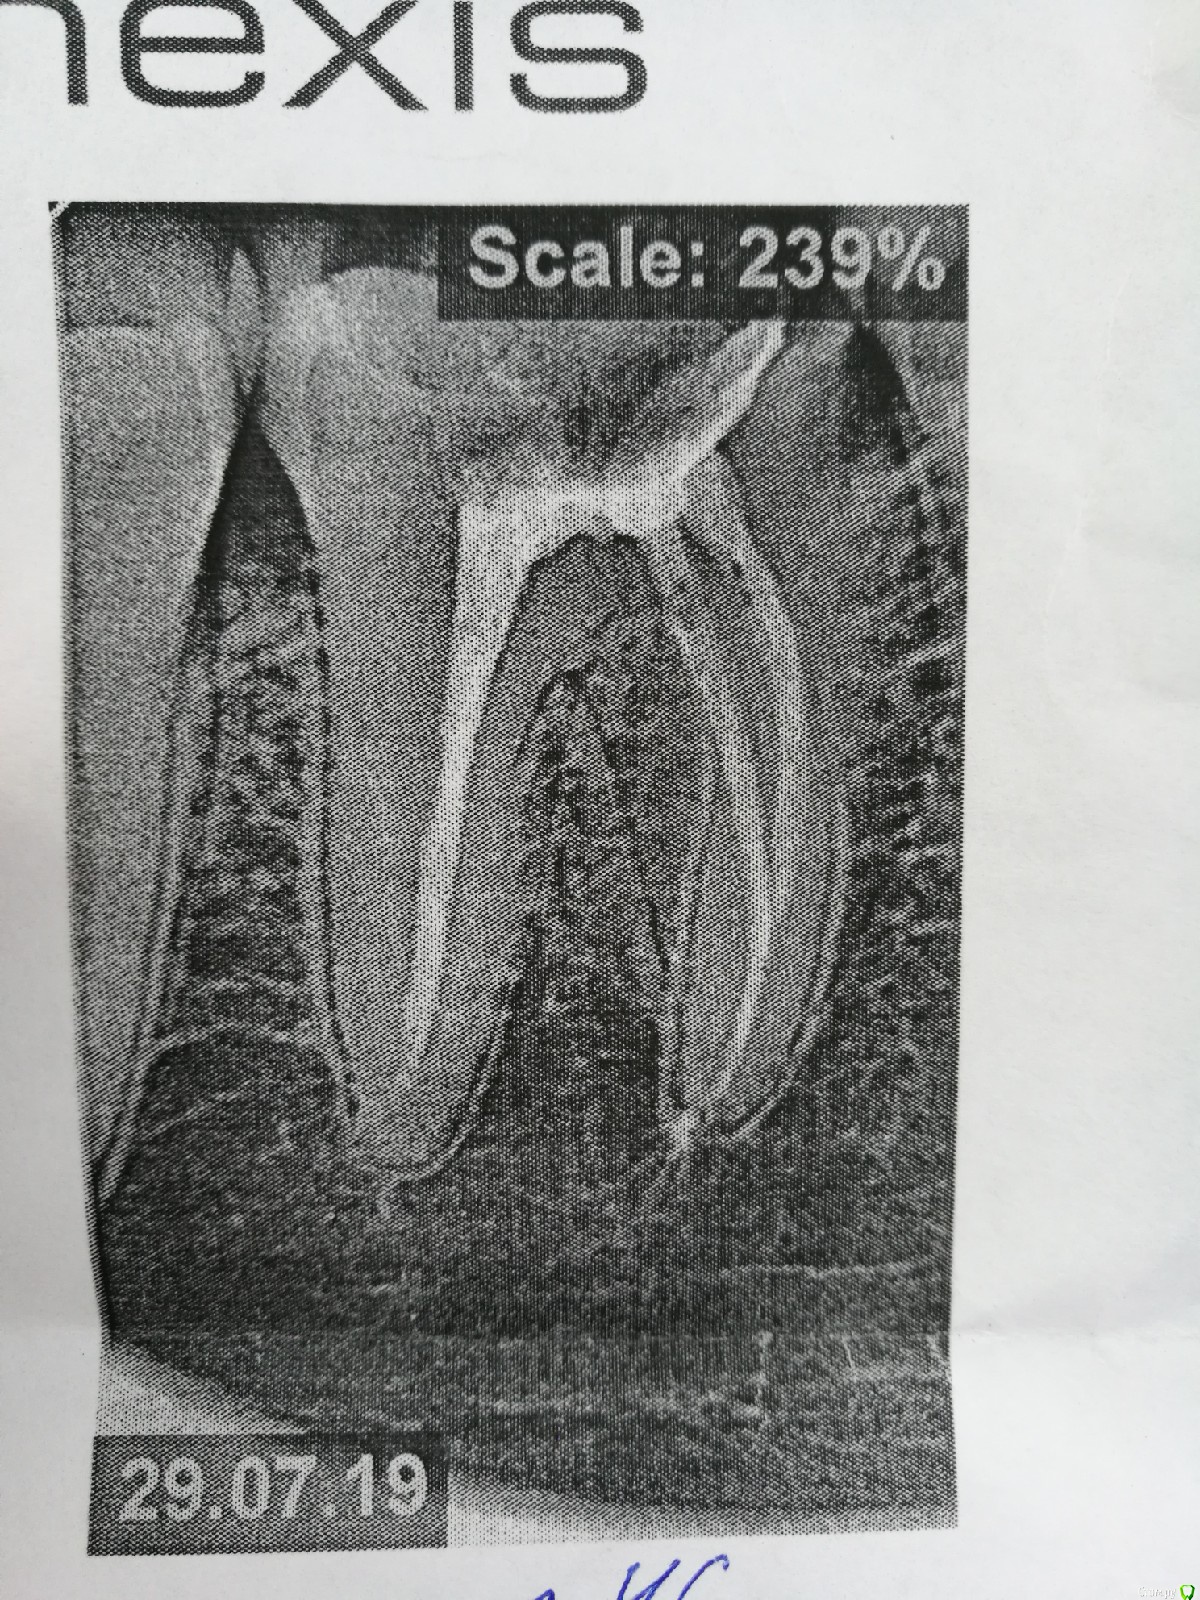

Юлия Китова Опубликовано 6 августа, 2019 Поделиться Опубликовано 6 августа, 2019 Здравствуйте, подскажите пожалуйста хорошо ли запломбированы каналы? Ссылка на комментарий

red_butler Опубликовано 6 августа, 2019 Поделиться Опубликовано 6 августа, 2019 На снимке все нормально, приступайте к протезированию зуба искусственной коронкой Ссылка на комментарий

Юлия Китова Опубликовано 6 августа, 2019 Автор Поделиться Опубликовано 6 августа, 2019 На снимке все нормально, приступайте к протезированию зуба искусственной коронкой а есть показания к коронке? у меня просто пока нет ни одной коронки,и я думала зуб должен быть разрушен на сколько то процентов..но у этого зуба лишь со стороны 5и разрушена стеночка Ссылка на комментарий

Doc Опубликовано 6 августа, 2019 Поделиться Опубликовано 6 августа, 2019 а есть показания к коронке? у меня просто пока нет ни одной коронки,и я думала зуб должен быть разрушен на сколько то процентов..но у этого зуба лишь со стороны 5и разрушена стеночкаДепульпирование зуба чаще всего уже само по себе есть показание к коронке. А если там еще и застревает пища, то тем более нельзя так оставлять. Либо полная реставрация, либо коронка. Ссылка на комментарий